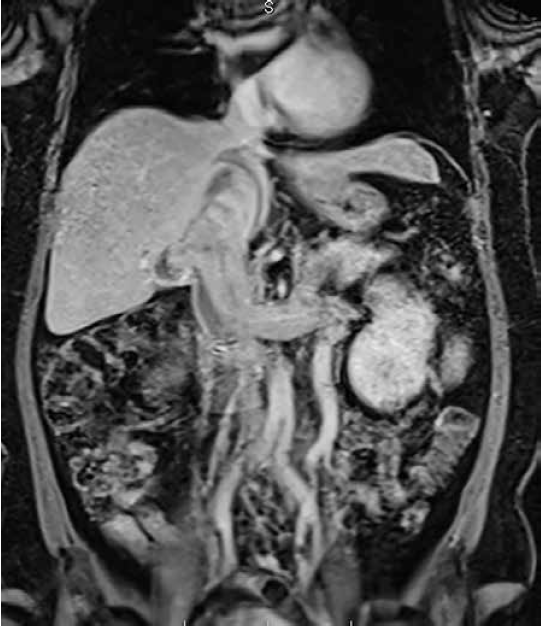

La clasificación de este tipo de trombos tumorales más usada, es la descrita por Neves y Zincke 6. El trombo de tipo I compromete la vena renal; el de tipo II, la vena cava inferior infrahepática; el de tipo III, la vena cava inferior retrohepática (figura 1), y el de tipo IV se extiende hasta la aurícula derecha. La evidencia es clara con respecto al abordaje quirúrgico de trombos de tipo I, pues en ellos el control vascular y la trombectomía no requieren una importante movilización hepática (figura 2). Los trombos de tipo IV requieren, inevitablemente, paro cardiaco y circulación extracorpórea 4.

La vena cava inferior retrohepática se diseca mediante la maniobra de movilización hepática completa (piggy-back), la cual se lleva a cabo mediante la liberación de los ligamentos triangulares derechos, exponiendo el área desnuda. Una vez identificada la cava, se ligan los ramos que drenan el hígado hacia ella; entre estos, se encontró el ramo venoso postero-inferior o vena de Mackuuchi, la cual llegó a diámetros de hasta 12 mm en nuestra serie. En este punto, se puede lograr la disección circunferencial de la cava por encima de la trombosis con mayor facilidad. Sin embargo, una vez logrados los reparos proximal y distal, no hubo necesidad de completar la disección en 360º, de hecho, con la exposición de la cara anterior o de 180 º de la circunferencia de vena cava inferior donde se encontraba la trombosis en toda su longitud, fue suficiente para lograr la potencial venotomía.

Antes de proceder al pinzamiento venoso por encima del trombo en la vena cava inferior, se hizo una evaluación imaginológica preoperatoria, y se utilizó la clasificación descrita por Ciancio, et al. 12 para definir el orden y la forma de pinzamiento (figura 3):

Trombos de tipo Neves IIIa. Se localizan por debajo del ostium de las suprahepáticas y permiten el pinzamiento de la vena cava inferior retrohepática por debajo, sin necesidad de la maniobra de Pringle o de pinzamientos de las venas suprahepáticas individualmente (figura 4).

Trombos de tipo Neves IIIb. Estos llegan hasta el ostium de las suprahepáticas, pero están por debajo del diafragma. Para el control adecuado, se usa la maniobra de Pringle y el pinzamiento individual de las venas suprahepáticas antes de su llegada, además de pinzar la vena cava inferior por encima del trombo.

Trombos de tipo Neves IIIc. Estos se extienden por encima del ostium de las suprahepáticas, pero por debajo del diafragma. Para lograr pinzar la vena cava inferior por encima del trombo, se debe abrir de forma longitudinal y anterior el diafragma, y exponer la vena cava inferior intrapericárdica. Lo anterior incluye pinzamientos del hilio hepático y de venas suprahepáticas.

Trombos de tipo Neves IIId. Estos se extienden por encima del ostium de las suprahepáticas y del diafragma, y llegan hasta la aurícula derecha sin ingresar en ella. Se deben usar las mismas maniobras que en los IIIc. Sin embargo, en este caso, el pinzamiento se puede hacer sobre la aurícula derecha y, después de pinzar las venas suprahepáticas, se puede proceder con una maniobra de ordeño, desplazando el trombo hacia el área de la venotomía.

Los pinzamientos se hacen en dirección distal a proximal, en el siguiente orden: vena cava inferior infrarrenal, renales contralaterales (arterial y luego venoso), pedículo vascular hepático, suprahepáticas (si es necesario), y vena cava inferior por encima del trombo. Posteriormente, se practica una venotomía longitudinal de aproximadamente de 5 a 10 cm, según la extensión del trombo. Una vez completada la trombectomía, se lava la vena cava inferior con una solución con 5.000 unidades de heparina no fraccionada, se sutura la cava en dos planos continuos con polipropileno 5.0 y se sueltan las pinzas en el mismo orden en que se colocaron (figura 5). Una vez completada la trombectomía, se continúa con la nefrectomía radical de la forma usual (figura 6). Se seleccionaron cinco pacientes con trombos de tipo Neves III, cuatro de ellos de tipo IIIa y -+uno de tipo IIIc.